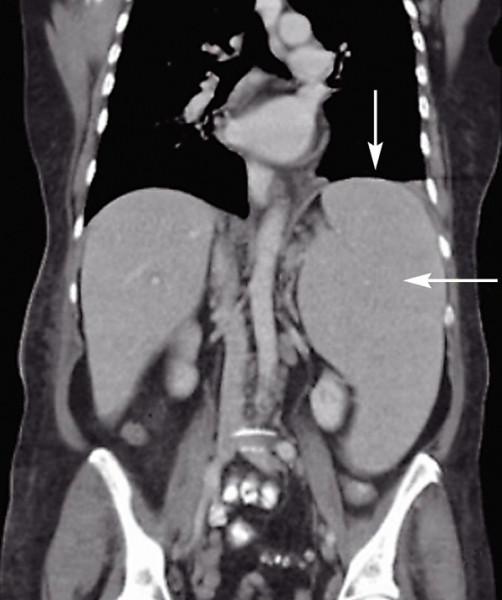

Snímek z počítačové tomografie (CT) ukazuje zvětšenou slezinu – splenomegalii (viz šipky) jako jeden z příznaků CLL. Převzato z Wikimedia Commons, v souladu s podmínkami použití